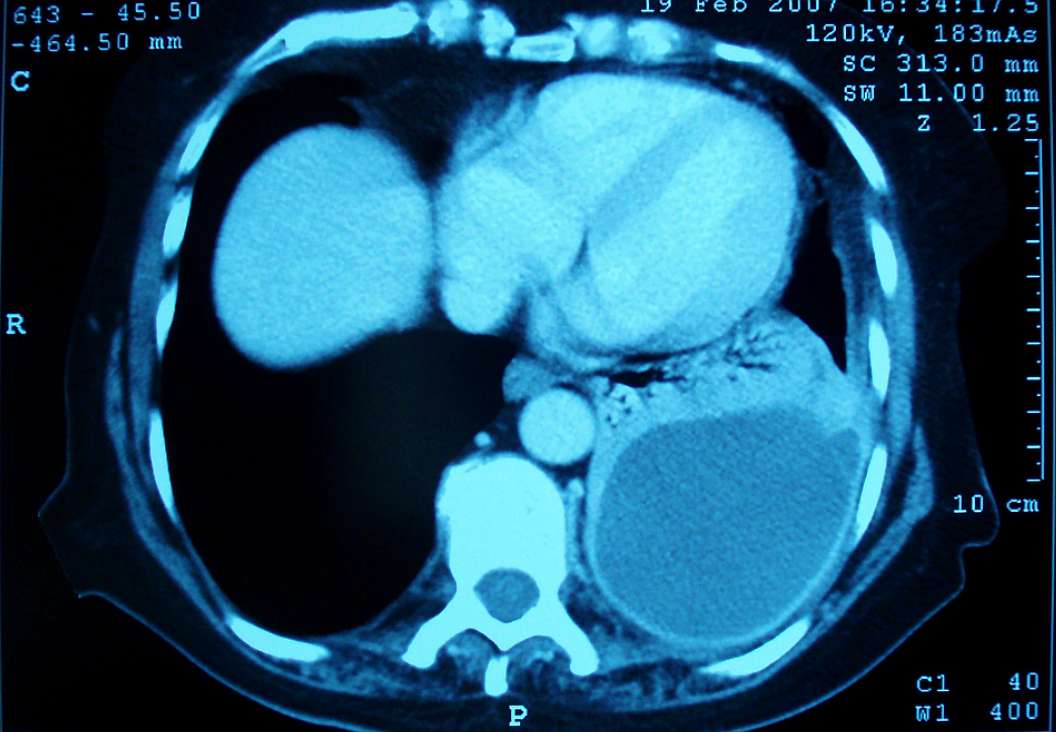

Imaging Findings

Chest X-ray (CXR) was reported as showing a cystic lesion at the left base with an air-fluid level seen within it. Contrast enhanced CT scan of chest demonstrated a fluid and air-filled cavity at the left lung base with an enhancing thick wall on coronal and axial images (see image). Patient was diagnosed with a left lower lobe lung abscess.

The patient was subsequently discharged to complete a further four weeks oral antibiotic therapy. Follow-up CT performed at 3 months showed almost complete resolution of the abscess on the coronal and axial images.